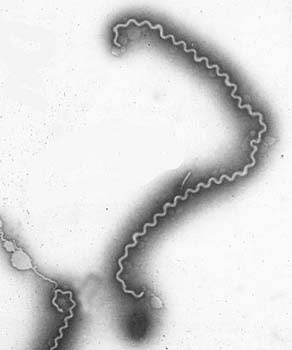

Лептоспиры: фотографии удивительных микроорганизмов